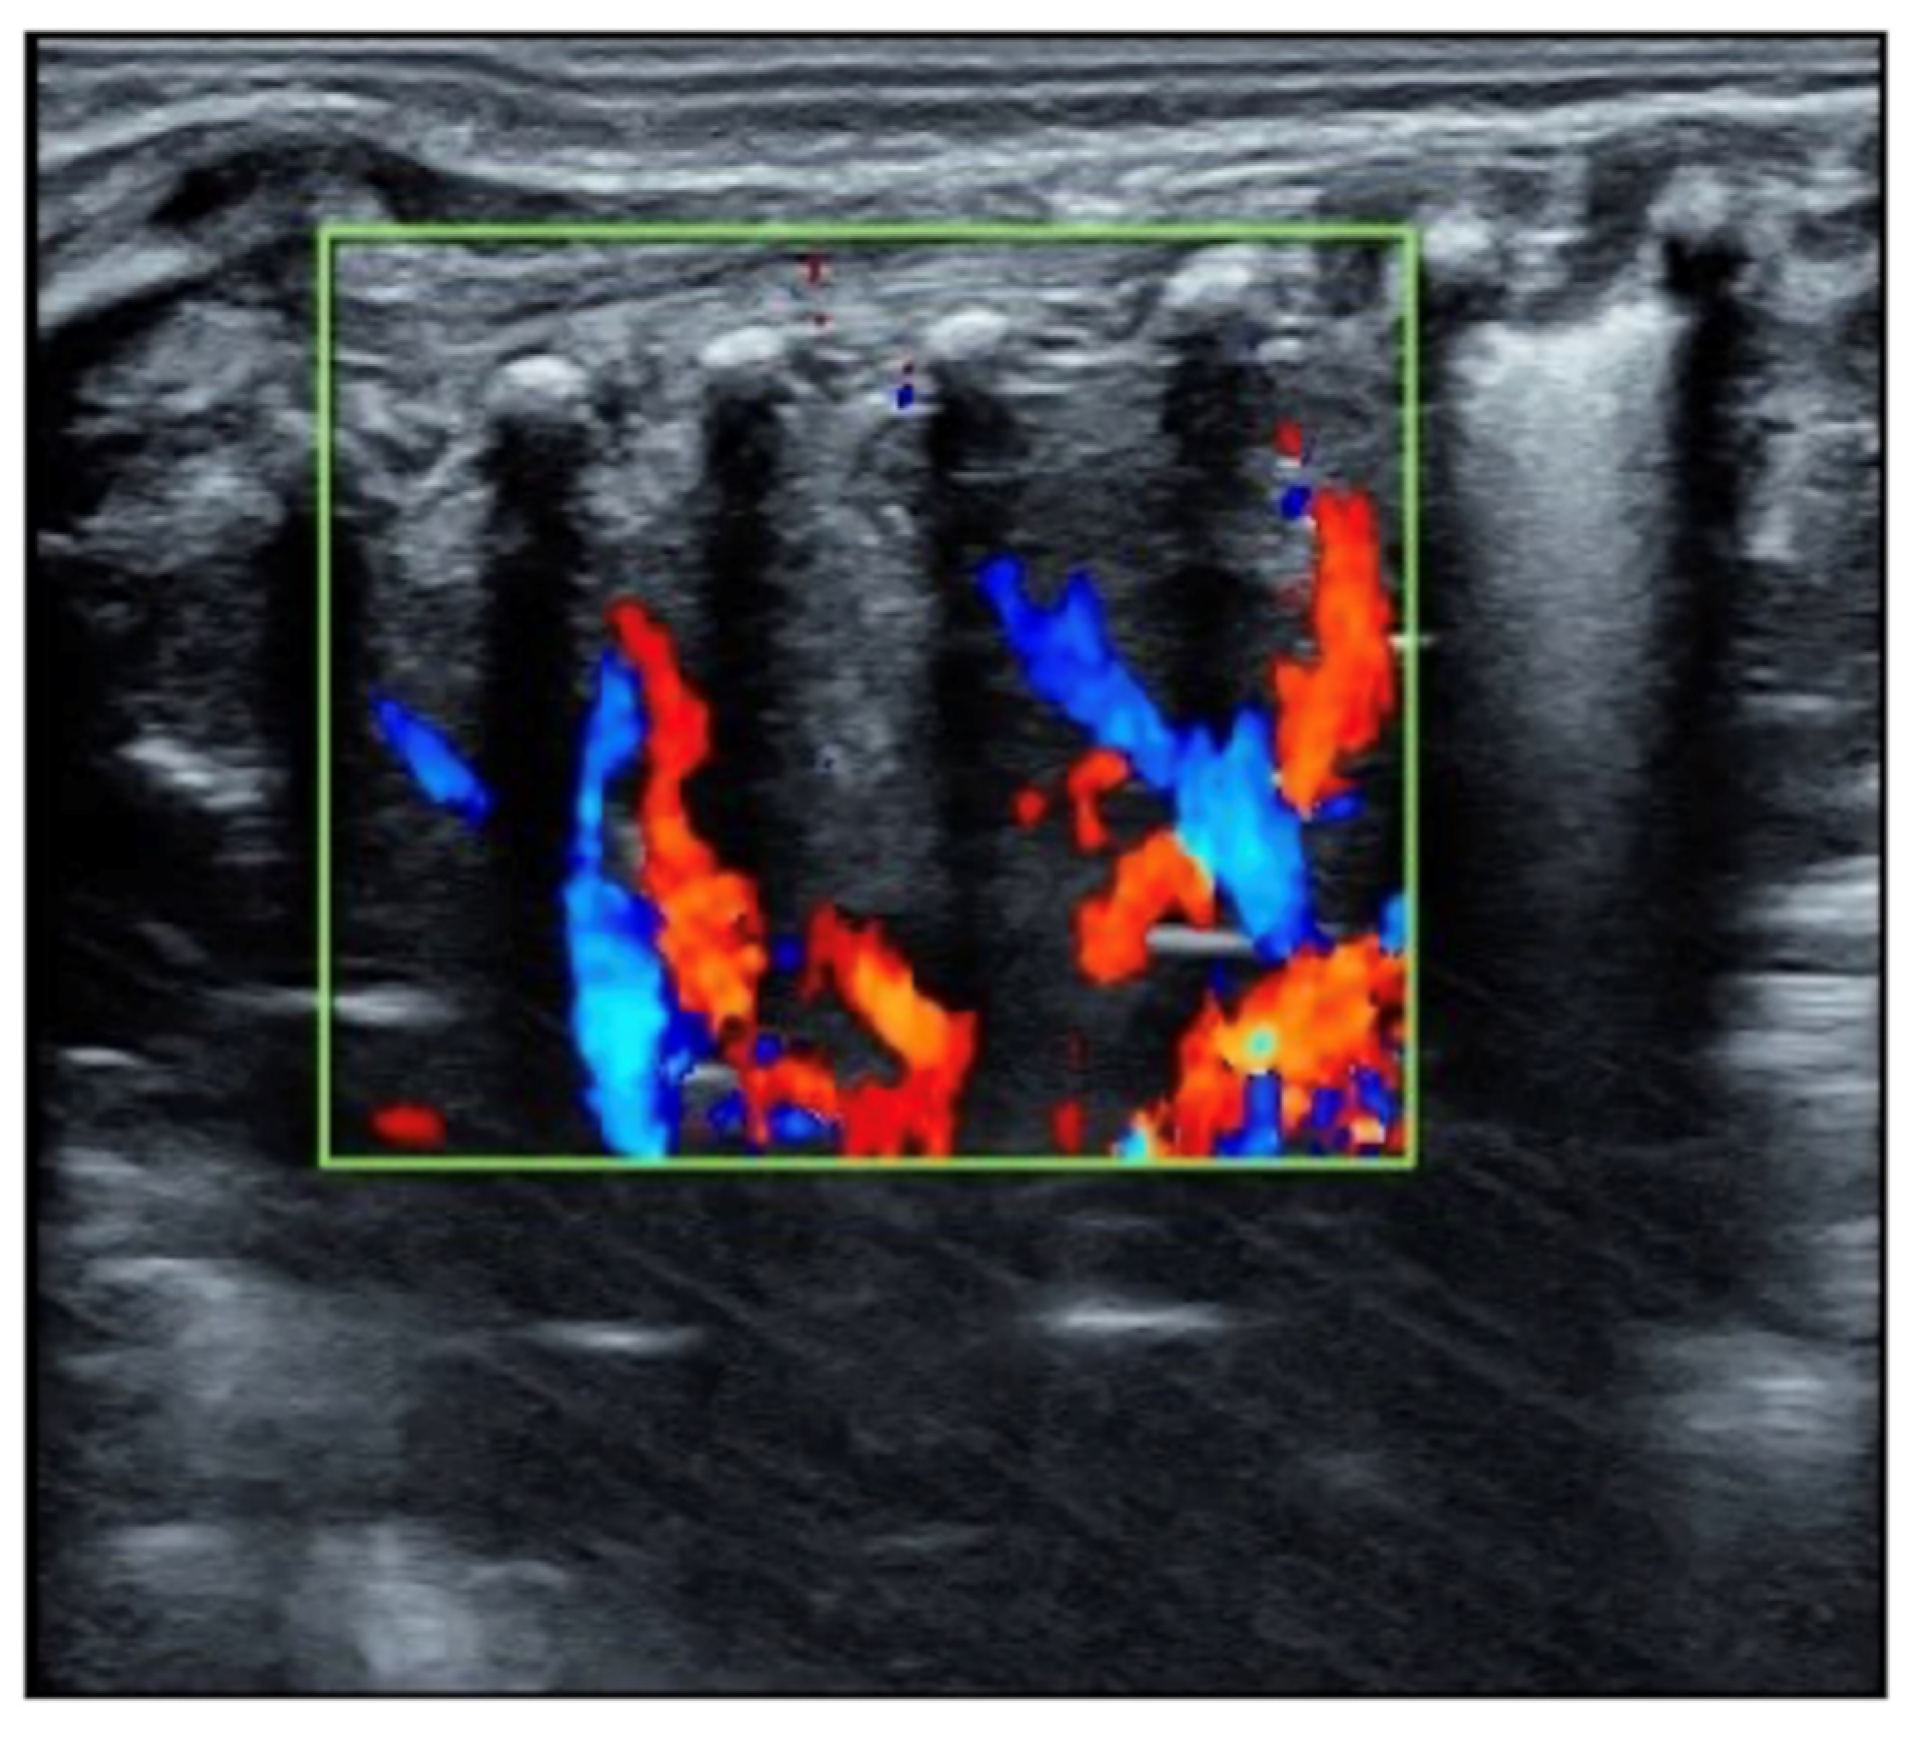

Figure 2.

Blood supply in the consolidated lung area; Doppler ultrasound showed that the blood supply existed within the consolidated area. The presence of blood supply in the lung tissue of consolidation is a prerequisite for the recovery of severe atelectasis.

The patient was a male premature infant delivered by cesarean section because of placental abruption at gestational age 28 weeks with a birth weight of 900 g. The infant was hospitalized at the NICU due to severe respiratory distress and subsequently complicated with diffuse intravascular coagulation (DIC) at the late stage of hyperfibrinolysis. A blood examination showed a white blood cell count (WBC) of 29.3 × 109/L and a c-reactive protein (CRP) of >150 mg/L (normally, <2.0 mg/L) at 4 h after birth. The patient’s condition stabilized after 10 days of invasive mechanical ventilation, anti-DIC and broad-spectrum antibiotic treatment. However, from the 14th day after birth, the infant had persistent fever (a temperature higher than 38 °C), and dyspnea reoccurred. The fever lasted for more than two weeks with a temperature >38 °C (highest 38.8 °C); the WBC count was elevated between a total of (21~29) × 109/L with a significantly elevated neutrophil ratio (>80%); the CRP increased (>150 mg/L for more than 2 weeks) for more than three weeks; the platelet count continued to decrease for more than 2 weeks (minimum <10 × 109/L); and three blood cultures and three deep sputum cultures and peripherally inserted central catheter (PICC) tip cultures showed no pathogenic bacterial growth. An LUS examination showed a large area of lung consolidation forming significant atelectasis in both lungs. The left lung mainly involved the upper lung field, while the right lung was almost consolidated in all lung fields (Figure 1). There was almost no bronchial inflation in the consolidation area, but a Doppler ultrasound showed that blood supply was still present well in the consolidated lung fields (Figure 2). This is very different from the normal lung images, which present as a bamboo sign on a B-mode ultrasound (Figure 3). During this period, the infant successively received meropenem, imipenem, linezolid, the fourth generation of cephalosporin, metronidazole and other antibiotics, and his condition still did not improve. Although both mycoplasma and chlamydia antibody/antigen tests were negative, when the antibiotics were adjusted to macrolide antibiotics (azithromycin) on day 28 postnatally, the temperature of the infant fell below 38 °C that day, and then, the temperature remained normal. Then, with the informed consent of the parents, blood samples were collected for metagenomic next-generation sequencing (mNGS) testing for pathogens, and the detection result confirmed legionella pneumophila infection. Therefore, the patient continued to receive azithromycin. The temperature remained normal, and the WBC, platelet and CRP levels gradually returned to the normal range within a week. The LUS showed that the scope of the lung consolidation gradually narrowed until it disappeared completely after 20 days (Figure 4). The total treatment period lasted for nearly 4 weeks, and the patient was discharged on the 70th day after birth, with a weight of 2620 g at that time. The infant was followed up for nearly 12 months and experienced normal growth. Over the past decade, LUS has been widely used in the diagnosis and differential diagnosis of neonatal lung diseases [3,4], including neonatal pneumonia [5,6,7]. LUS has a number of advantages over CXR; it should serve as a complementary diagnostic method in providing accurate, timely and reliable information [8,9]. The major finding of the LUS examination in this patient was the large-area consolidation in the bilateral lungs. There were a few air bronchograms in the consolidation area of the left lung but no air in the consolidated area of his whole right lung, which meant serious atelectasis (Figure 1). However, Doppler ultrasonography showed that there was still good blood supply in the lung tissues with consolidation and atelectasis (Figure 2). The presence of blood supply is a prerequisite for the consolidation and atelectasis of lung tissue to recover to normal [2].